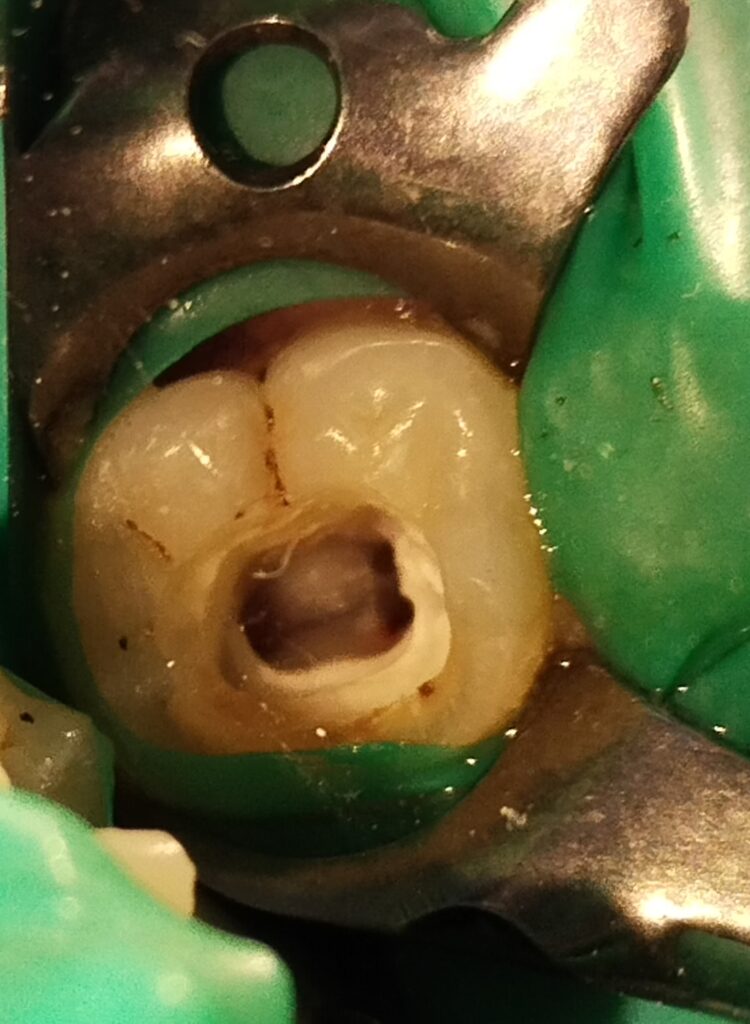

Treatment Process: The root canal treatment was performed in two visits. During the first visit, pulpectomy was carried out, followed by the placement of non-setting calcium hydroxide in the canals for disinfection. The patient reported no pain after the first visit, indicating successful alleviation of symptoms.

In the second visit, the canals were obturated, and the tooth was filled with composite material to restore its function and appearance. The patient tolerated the procedure well, with no pain reported during the visit.

Outcome: Radiographs taken before, during, and after the root canal treatment revealed that the tooth was properly cleaned, shaped, and obturated, ensuring the success of the treatment.